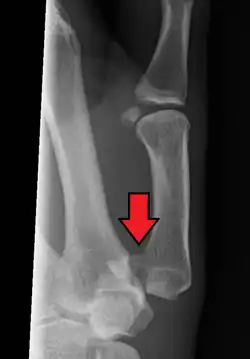

Bennett's fracture or Bennett fracture is a type of partial broken finger involving the base of the thumb, and extends into the carpometacarpal (CMC) joint.[1]

This intra-articular fracture is the most common type of fracture of the thumb, and is nearly always accompanied by some degree of subluxation or frank dislocation of the carpometacarpal joint.

In the case of the Bennett fracture, the proximal metacarpal fragment remains attached to the anterior oblique ligament, which in turn is attached to the tubercle of the trapezium bone of the CMC joint. This ligamentous attachment ensures that the proximal fragment remains in its correct anatomical position.

The distal fragment of the first metacarpal bone possesses the majority of the articular surface of the first CMC joint. Unlike the proximal fracture fragment, strong ligaments and muscle tendons of the hand tend to pull this fragment out of its correct anatomical position.

Though these fractures commonly appear quite subtle or even inconsequential on radiographs, they can result in severe long-term dysfunction of the hand if left untreated. In his original description of this type of fracture in 1882, Bennett stressed the need for early diagnosis and treatment in order to prevent loss of function of the thumb CMC joint, which is critical to the overall function of the hand.[4]